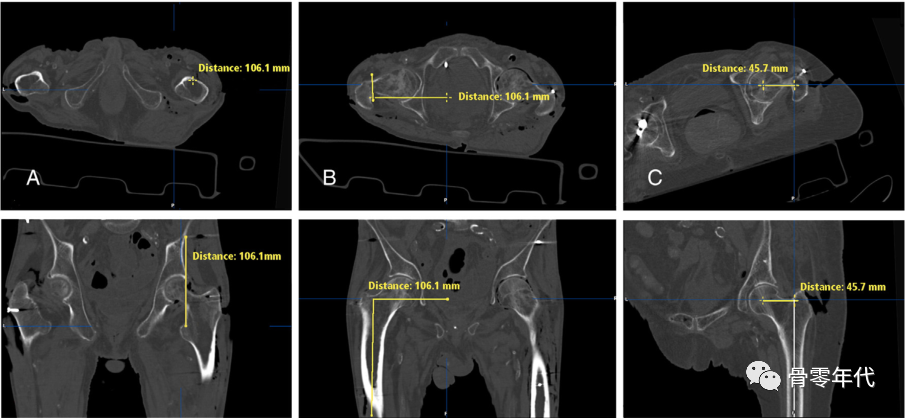

(A)对CT测量,确定了基准地标。然后分析骨盆旋转(B),测量LL、GO和FO的变化(C)。

采用基准点三维ct测量LL (A)、GO (B)和FO (C)变化。对于LL,指小转子上侧面通过ASIS到横平面的距离。从耻骨结节到股轴的垂直距离定义了GO。对于FO测量,创建了Sariali等人描述的特定股骨框架